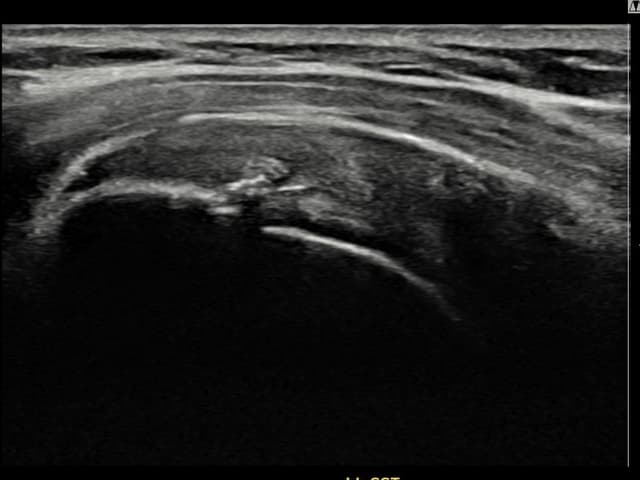

[촬영시기:22.10.06~22.11.14]

[어깨인대 축소봉합술] 좌측 어깨 극상근건 광범위 파열로 수개월간 일상생활이 어렵던 중 내원하셨습니다.